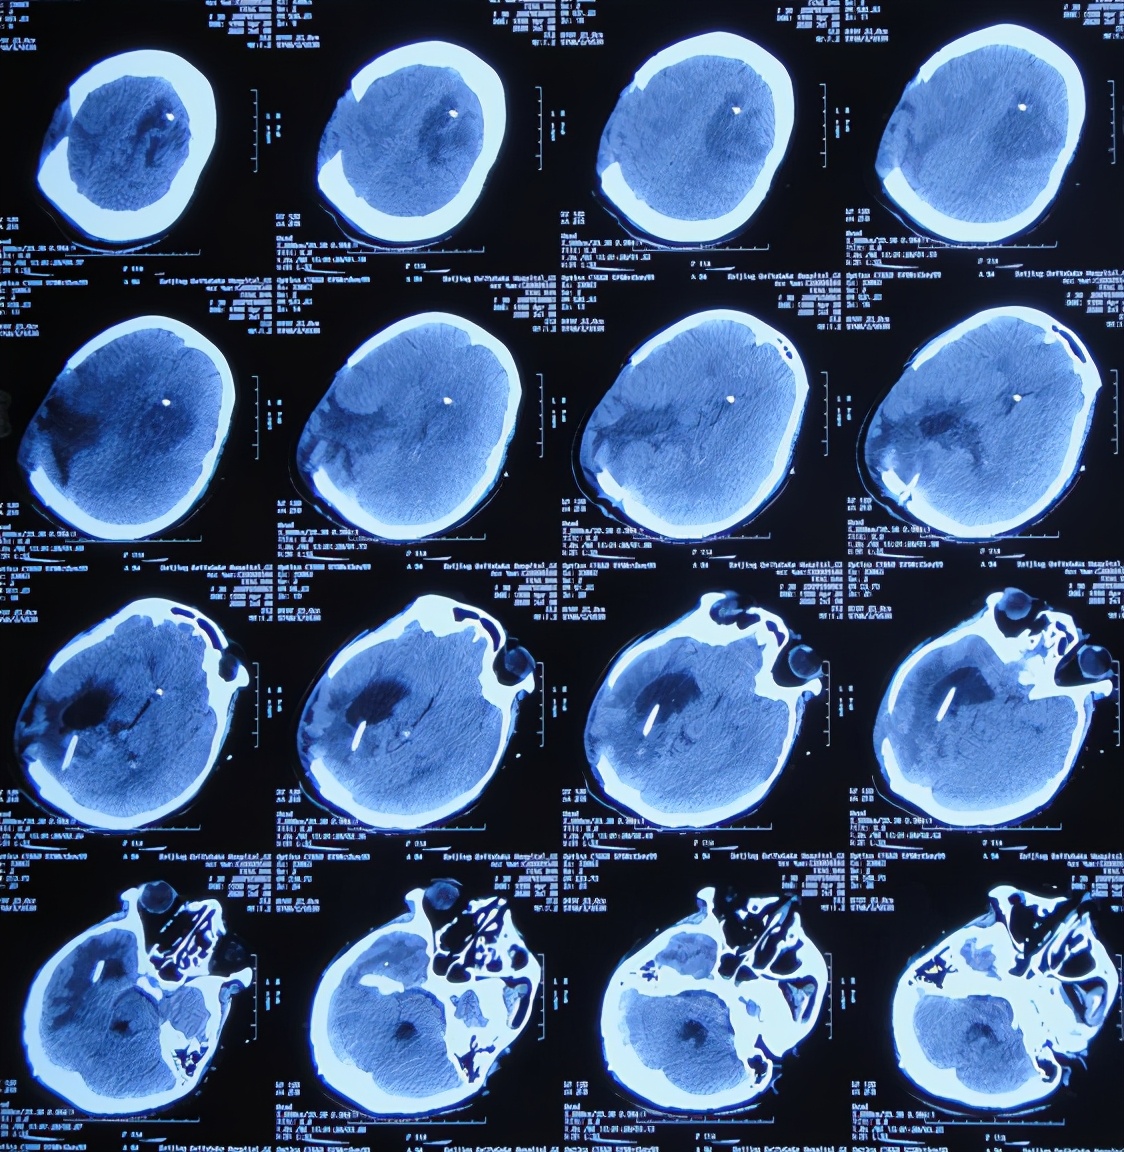

患者于2020年4月2日,在公司上班时突发头痛呕吐,急诊至陕西省西安市某二级医院,急诊查头颅CT检查示右顶叶脑出血破入脑室( 图-1 ),全脑血管造影示脑血管畸形(片子丢失);进行了开颅脑血管畸形切除术+去骨板减压术,术中留置引流外管;术后当天转入ICU继续治疗。

图-1: 2020年4月2日头颅CT